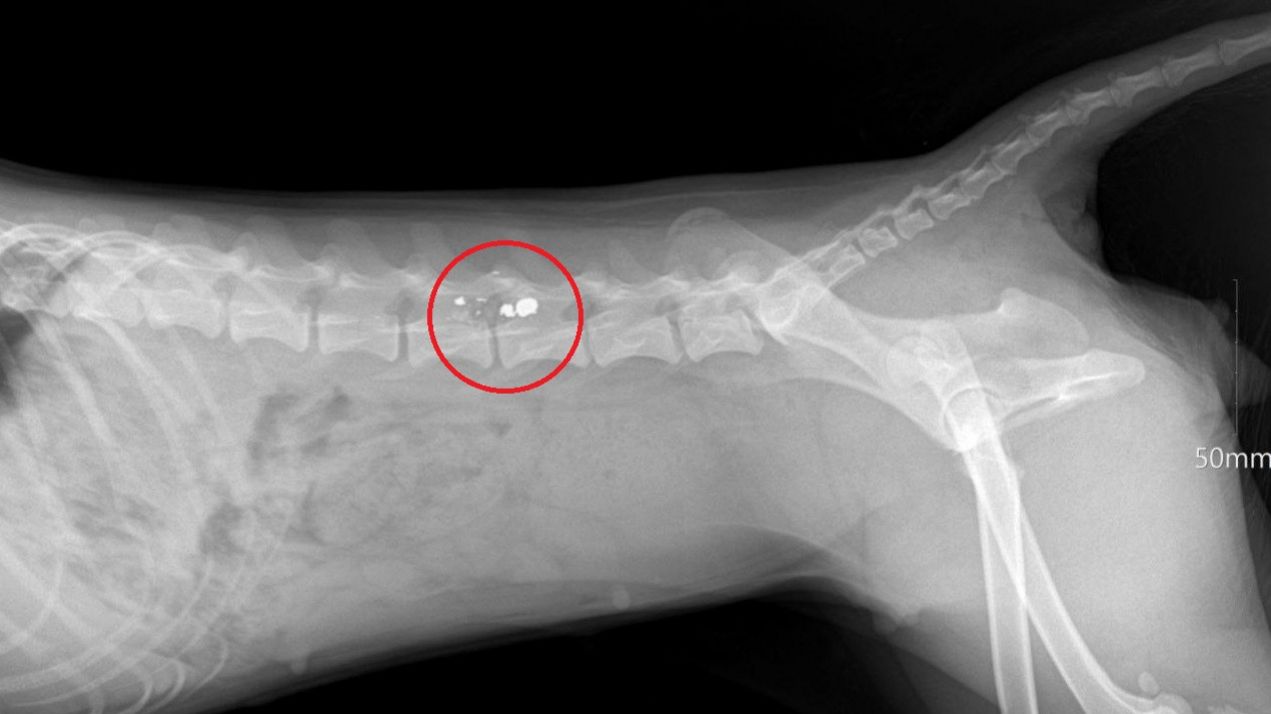

Хозяева доставили собаку в ветеринарную клинику. Врачи диагностировали травмы, которые привели к параличу задних лап.